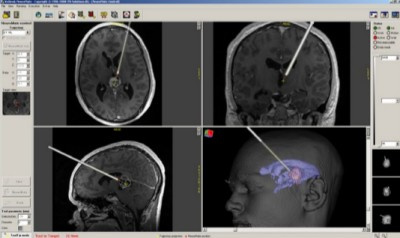

Zpětná vazba k poloze hrotu sondy v reálném čase na navigační stanici neuromate. Tumor v oblasti corpus pineale je znázorněn fialově.Specializovaní roboti se úspěšně prosazují zejména ve stereotaktické neurochirurgii, která je díky minimálnímu zásahu do těla pacienta velmi šetrná. Využívá trojrozměrný souřadnicový systém k lokalizaci míst uvnitř nitrolebního prostoru. Podobně jako u obráběcích strojů se hlava pacienta fixuje pomocí stereotaktického rámu, který kromě fixace hlavy přesně definuje operační pole ve speciálním softwaru souřadnice X, Y a Z.

Neurochirurg ovládá kloubové robotické rameno. Hlava pacienta je upevněna v rámu k základně robota. Robot přesně nasměruje chirurgické nástroje do polohy na základě vyšetření na výpočetní tomografii (CT). Při vlastní operaci se rameno robota díky přesným souřadnicím zaměří na cílový bod, který může představovat místo pro stimulaci mozku při léčbě epilepsie, nádor či absces. Poté se provede návrt lebeční kosti, který má u biopsie průměr 2,1 mm, v případě hluboké mozkové stimulace 14 mm. Nástroj poté pronikne do nitrolebního prostoru a následně do cílového bodu. Podle typu výkonu se může zavést stimulační sonda, odebere se vzorek tkáně k histologickému vyšetření či se provede punkce abscesu odsátím zánětlivého ložiska.